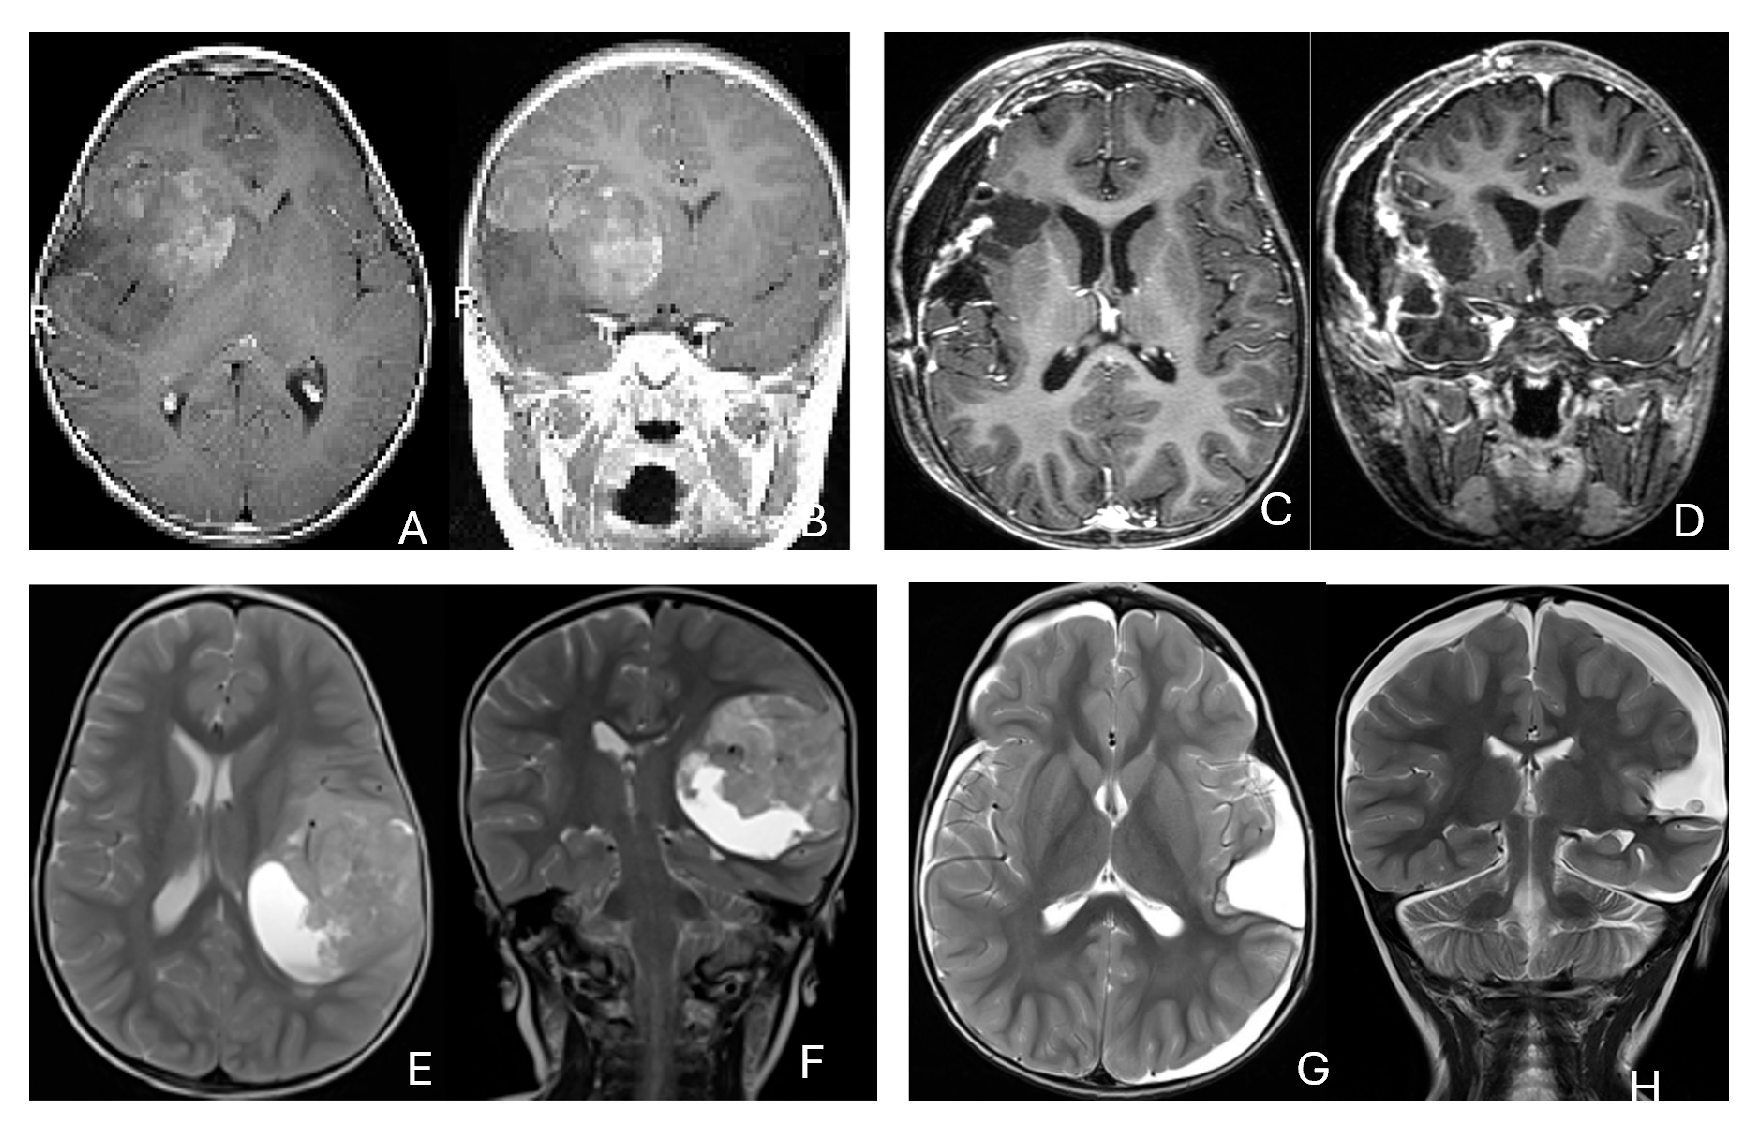

The cerebellar peduncular, vermis, and CPA/CMF are common site of ATRTs. Most ATRT-TYR tumors arise from the middle cerebellar peduncle and inferior vermis [76] and can extend exophytically into the cerebellopontine angle (CPA) and cerebellomedullary fissure (CMF). ATRT-MYC tumors can originate from cranial nerves in the CPA, producing imaging appearances that overlap with TYR tumors; however, the age distribution differs, with TYR typically affecting much younger children than MYC. Infratentorial ATRTs frequently mimic posterior fossa ependymomas in their location and propensity to extend into the CPA and fourth ventricle, but ATRTs tend to be more infiltrative, whereas ependymomas are usually expansile and less invasive [77]. Consistent with this pattern, the European Rhabdoid Registry reports cranial nerve involvement occurs in approximately 3% of ATRT cases and is most often associated with the MYC subgroup [62]. One female patient with CPA ATRT of CPA, who was notably the oldest in this cohort, had a tumor that likely originated from the vestibular nerve, without involvement of the brainstem or cerebellum. (Figure 12).

Figure 12.

CPA ATRT. (A–D): MR images ((A): axial; (B): coronal) of a 20-year-old girl, the oldest in this cohort, who presented with left-sided hearing loss and partial facial weakness, reveal ATRT that appears to originate from the vestibular nerve. Surgical findings and post-resection MR images ((C): axial; (D): coronal) indicate no tumor invasion into the cerebellum or brainstem, which contrasts with typical presentations of infantile ATRT.